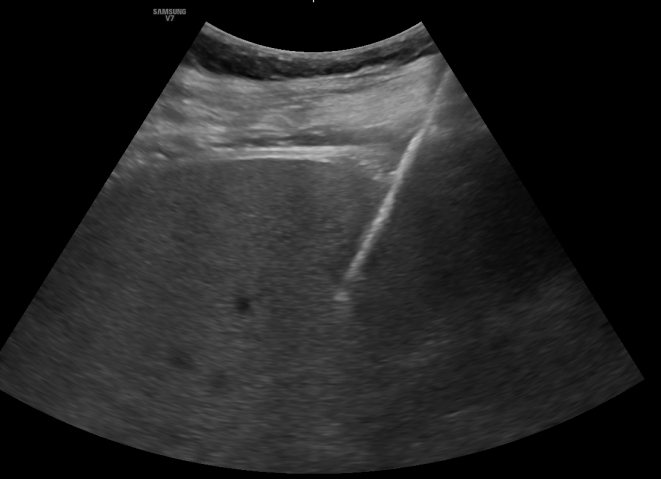

However, the strongest predictor of LTP remains the minimal ablative margin (MAM), while MRI serves as a valuable complementary tool within a multimodal approach to optimize outcomes.